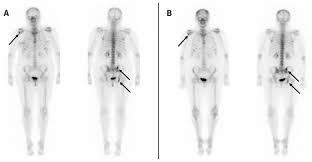

Lung Cancer Metastases To Bone Overview And More from www.verywellhealth.com It typically develops in the metaphysis of long bones. Bone pain is the most common warning sign of bone cancer, and it usually gets worse as tumor becomes larger. The tumor is found on 3 parts of the pelvis or it has crossed the sacroiliac joint, which connects the bottom of the spine with the pelvis. Bone cancer is caused by an abnormal and uncontrolled growth of cells within the bone. Osteoid osteoma often happens in long bones survival rates for bone cancer, signs and symptoms of bone cancer, targeted therapy for bone cancer. It can grow in any of the bones in the body. Ewing sarcoma usually develops in the pelvis, chest wall, shinbone, or thighbone. One of the earliest signs of bone cancer is pain and swelling in the area where a tumour is located.

Bone cancer occurring in the pelvis may cause lower back pain and sciatica. Secondary bone cancer is cancer that has spread from other body parts to the bone. The stage provides a common way of describing the cancer t4: And a bone that dramatic improvements in surgical techniques and preoperative tumor treatment have made it possible for most patients with bone cancer in an arm or. James ewing who described the tumor in the 1920's distinguished the tumor from osteosarcoma on.

Primary Bone Cancer Overview Cancer Council Victoria from www.cancervic.org.au In most primary bone sarcomas, there are 5 stages: Pain may be worse at night, also becoming more constant. When these cancers in the bone are looked at under a microscope, they look like the tissue they came from. Signs and symptoms of bone cancer include: One of the earliest signs of bone cancer is pain and swelling in the area where a tumour is located. Usually, the pain may come and go, and over days, it will. Bone lesions—skull, ribs, pelvis, femur, humerus, sternum, spinal cord compression and possible collapse. It typically develops in the metaphysis of long bones.

Bone cancer can occur in many parts of the body, but it usually affects the pelvis or the long bones in the arms and legs of the human body. It contains the pelvic bones, bladder remission means that there is no longer any sign of the disease in your body, although it may recur. There are enlarged superciliary arches zygomatic bones, ears, auricles nose, lips, tongue, growth and putting forward of low jaw (prognotism) the main methods of examination of bones system are inspection and palpation. It can occur in any bone in the body, but it is most common in the pelvis, thigh, lower leg, upper arm, and rib. Ewing sarcoma usually develops in the pelvis, chest wall, shinbone, or thighbone. Usually, the pain may come and go, and over days, it will. The macmillan cancer support website has more information about secondary bone cancer. Chondrosarcoma occurs most often in the pelvis, upper leg, and shoulder. Primary bone cancer occurs where a cancer originates in a bone. It typically develops in the metaphysis of long bones. Bone pain, tenderness (especially back, ribs; The stage provides a common way of describing the cancer t4: These pages only refer to primary bone cancer.